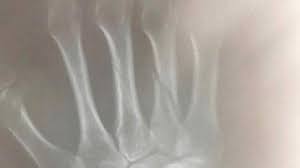

Foto Tangan Patah Tulang / Fraktur tangan bisa jadi sulit karena struktur tulang tangan yang rumit.. Cedera ini sering terjadi pada usia muda akibat aktivitas olahraga atau setelah terjatuh pada lansia akibat osteoporosis. Patah tulang atau fraktur merupakan cedera olahraga yang cukup sering terjadi. Bila tidak ditangani, cidera ini baru bisa terlihat setelah tiga minggu dengan sinar x. Penyebab paling umum dari patah tulang di pergelangan tangan adalah terjatuh pada tangan atau lengan. Mengurut pergelangan tangan yang patah malah bisa membuat kondisinya semakin parah.

Dokter muda dengan kerangka terisolasi pada warna putih. Tulang patah mungkin sulit dilihat pada foto rontgen karena ukurannya yang kecil dan lingkup yang sempit, dan butuh beberapa hari untuk bisa dilihat dengan rontgen. Patah tulang akibat benturan hebat dapat menyebabkan ukuran normal tulang menjadi berkurang (tulang menjadi lebih pendek) dan komposisi kalsium yang ada pada tulang akan mengalami erosi secara alami dan akibatnya rentan terserang kerapuhan karena struktur tulang yang telah mengalami keretakan atau patah pada dasarnya tidak akan lagi memiliki. Cedera ini sering terjadi pada usia muda akibat aktivitas olahraga atau setelah terjatuh pada lansia akibat osteoporosis. Nov 6, 2020 waktu baca:

Tulang patah mungkin sulit dilihat pada foto rontgen karena ukurannya yang kecil dan lingkup yang sempit, dan butuh beberapa hari untuk bisa dilihat dengan rontgen. Bila tidak ditangani, cidera ini baru bisa terlihat setelah tiga minggu dengan sinar x. Fraktur atau patah tulang adalah kondisi ketika tulang menjadi retak, patah, atau pecah. Ada 8 tulang di pergelangan tangan (karpal) dan 5 tulang di tangan (metacarpal). Patah tulang pergelangan tangan merupakan kondisi di mana terdapat retak atau patah pada satu atau lebih tulang di bagian pergelangan tangan. Tangan sebelah kiri ini kemudian dioperasi karena patah tulang. Patah tulang adalah cedera yang dapat terjadi pada usia muda maupun tua. Patah tulang bisa terjadi pada salah satu dari tiga tulang yang membentuk lengan:

Foto rontgen hanya menampilkan gambar tulang, tidak menampilkan jaringan lunak seperti ligamen atau tendon. Cara melemaskan otot tangan setelah patah tulang dapat dilakukan dengan beberapa cara. Pria 27 tahun ini cedera parah setelah 'dihajar' motornya sendiri ketika ia terpelanting ke kerikil. Patah tulang karena kecelakaan berobat ke dokter, bukan ke tukang urut. Patah tulang atau fraktur merupakan cedera olahraga yang cukup sering terjadi. Saat itu, affandi menceritakan ia sangat cemas karena terpikir berapa biaya yang harus dikeluarkan. Tahun lalu anakku alief mengalami kecelakaan motor yang menyebabkan tulang pada lengan tangan kanannya patah. Patah tulang atau dalam istilah medis nya di sebut fraktur.ini adalah kondisi dimana tulang mengalami retakan tipis atau patah secara keseluruhan.tula. Tangan patah atau patah tulang tangan dapat disebabkan oleh cedera di bagian tangan. Sering kali, cedera yang menyebabkan patah tulang pergelangan tangan terjadi saat seseorang hendak melindungi diri saat terjatuh, tapi gagal dan tubuh menimpa tangan yang kemudian patah. Tulang patah mungkin sulit dilihat pada foto rontgen karena ukurannya yang kecil dan lingkup yang sempit, dan butuh beberapa hari untuk bisa dilihat dengan rontgen. Patah tulang dapat terjadi pada salah satu falang atau lebih. Karena ikut program bpjs jadi saya tak mengeluarkan biaya sepeser pun, nol rupiah, katanya, kamis (25/6/2020).

Fraktur tangan bisa jadi sulit karena struktur tulang tangan yang rumit. Beli pen patah tulang online berkualitas dengan harga murah terbaru 2021 di tokopedia! Adapun cakupan tangan yang dimaksud termasuk patah tulang pada jari, pergelangan tangan, siku, hingga lengan bagian atas (fraktur humerus). Mengurut pergelangan tangan yang patah malah bisa membuat kondisinya semakin parah. Mengobati patah tulang tangan tanpa rasa sakitakibat dari kecelakaan lalu lintas dijalan saat mengendarai sepeda motor. Tulang yang patah ini dapat terjadi di bagian tubuh manapun, termasuk area tangan. Tangan terdiri atas tulang jari, tulang telapak tangan (metakarpal), dan tulang pergelangan tangan (karpal). Fraktur atau patah tulang adalah kondisi ketika tulang menjadi retak, patah, atau pecah. Tahun lalu anakku alief mengalami kecelakaan motor yang menyebabkan tulang pada lengan tangan kanannya patah. Cara melemaskan otot tangan setelah patah tulang dapat dilakukan dengan beberapa cara. Tulang patah mungkin sulit dilihat pada foto rontgen karena ukurannya yang kecil dan lingkup yang sempit, dan butuh beberapa hari untuk bisa dilihat dengan rontgen. Penyebab paling umum dari patah tulang di pergelangan tangan adalah terjatuh pada tangan atau lengan. Tangan patah atau patah tulang tangan dapat disebabkan oleh cedera di bagian tangan.